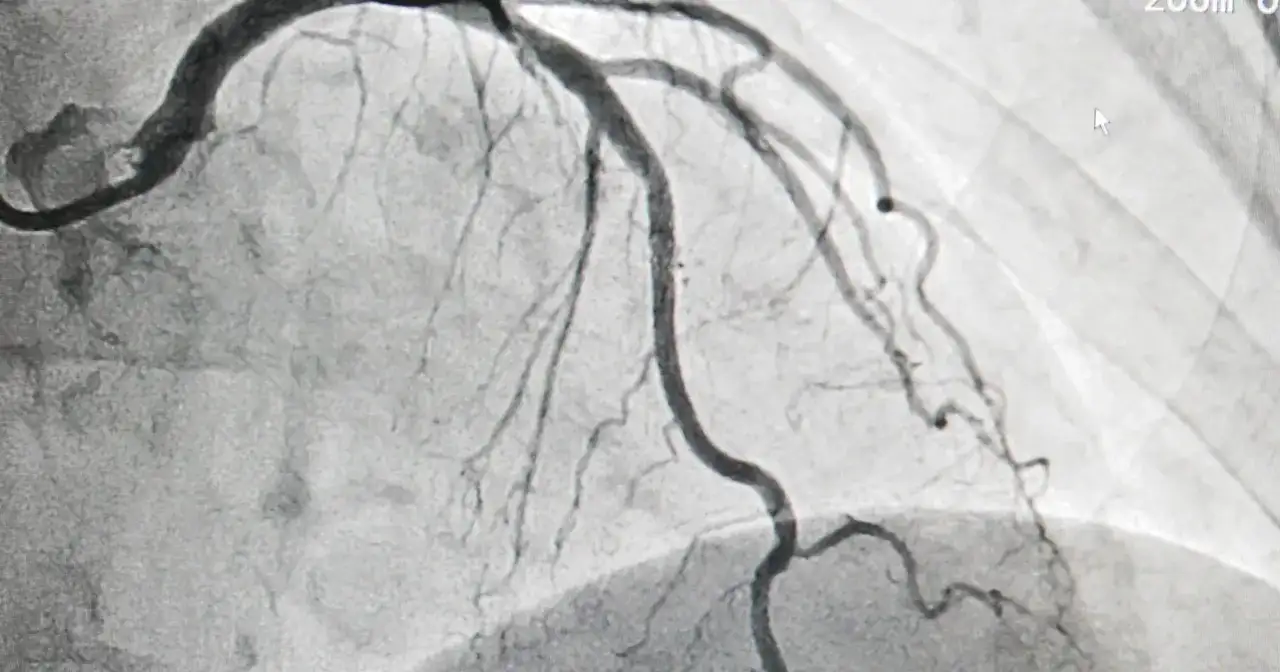

Dowiedz się, kiedy przysługuje odszkodowanie za koronarografię, co to są błędy medyczne i jak skutecznie dochodzić roszczeń.